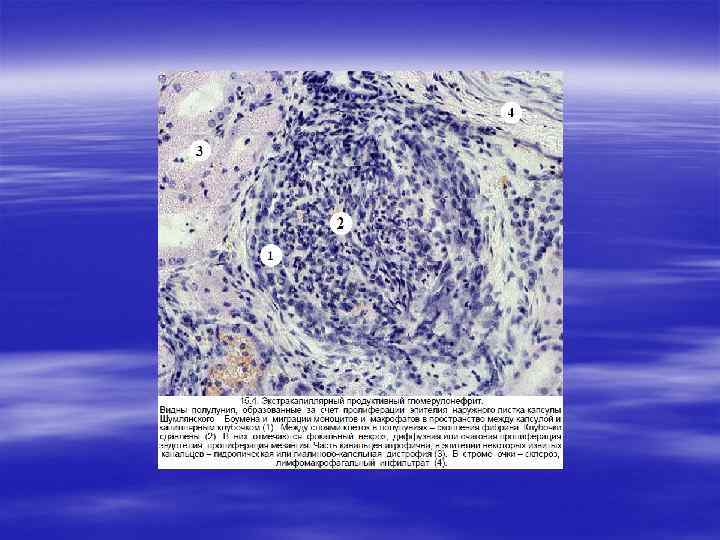

БЫСТРОПРОГРЕССИРУЮЩИЙ ГЛОМЕРУЛОНЕФРИТ § Эта форма гломерулонефрита представляет собой полиэтиоло гическийсиндром, отличающийся от описанных форм гломеруло нефритовсвоим злокачественным течением, экстракапиллярной локализацией патологического процесса. § Отличи тельной особенностью данного вида гломерулонефрита является пролиферация клеток париетального эпителия капсулы Шумлянского — Боумена с образованием в большинстве клубочков инфильтрированных моноцитами и макрофагами характерных полулуний.

§ В зависимости от причин развития быстропрогрессирующий гломерулонефрит разделяют на три категории: § I. Постинфекционный (постстрептококковый, вирусный). § II. Ассоциированный с системными заболеваниями: системная красная волчанка, полиартериит, синдром Гудпасчера, гранулематоз Вегенера. § III. Идиопатический, первичный.